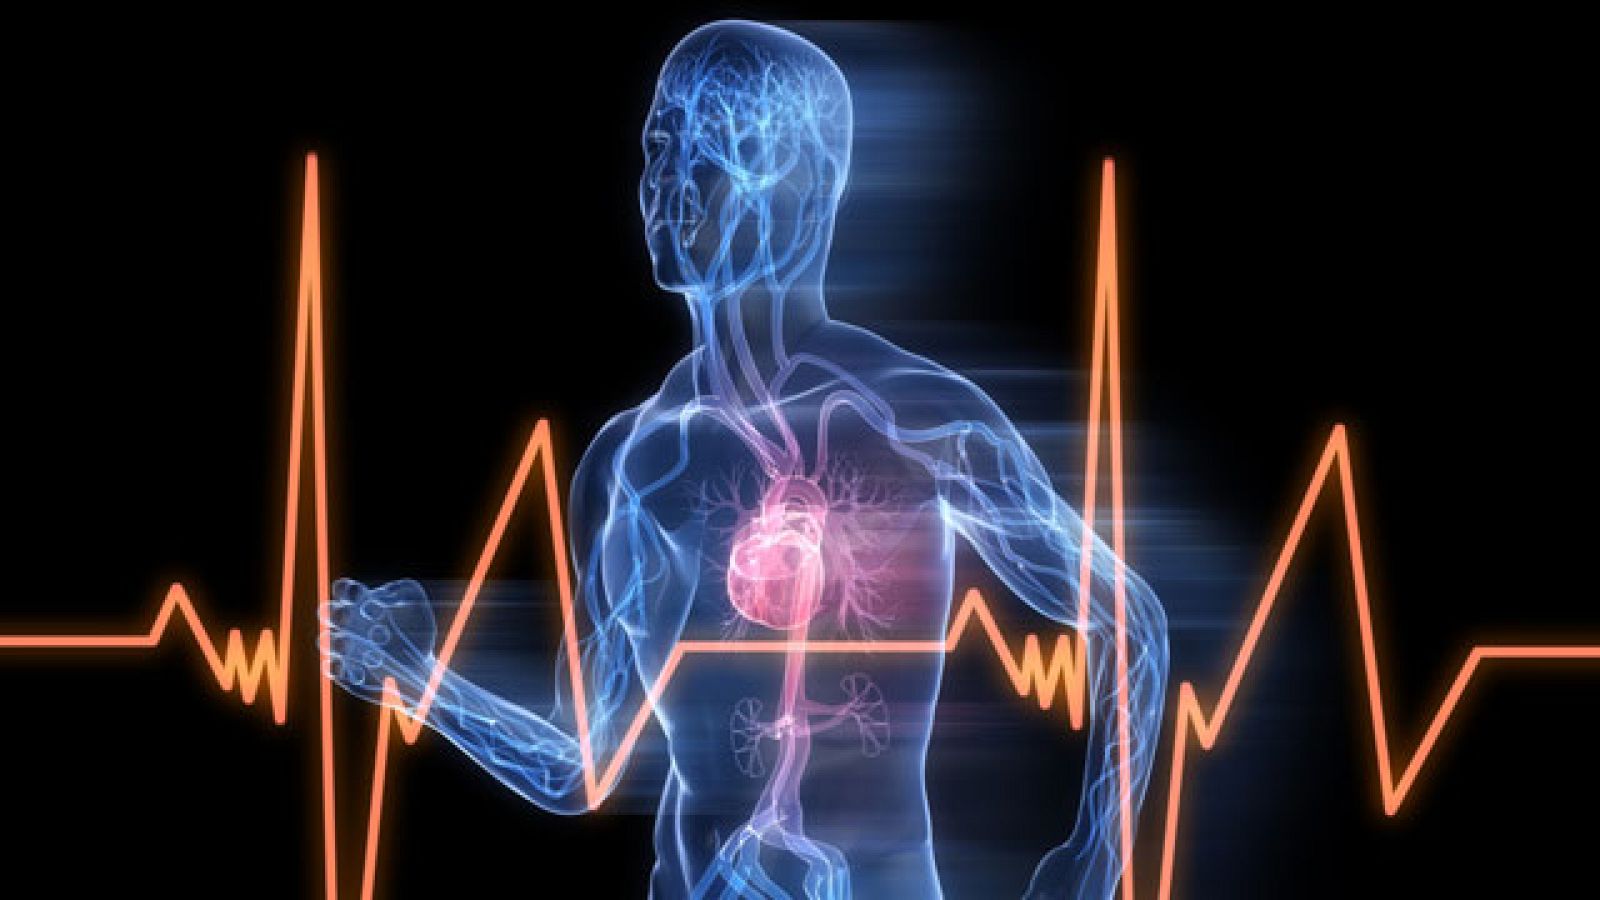

Taquicardias, arritmias ...

Hablamos del corazón y de algunas dolencias que pueden acabar siendo mortales ¿Cómo detectarlas? ¿Cómo saber que debemos acudir con urgencia al...